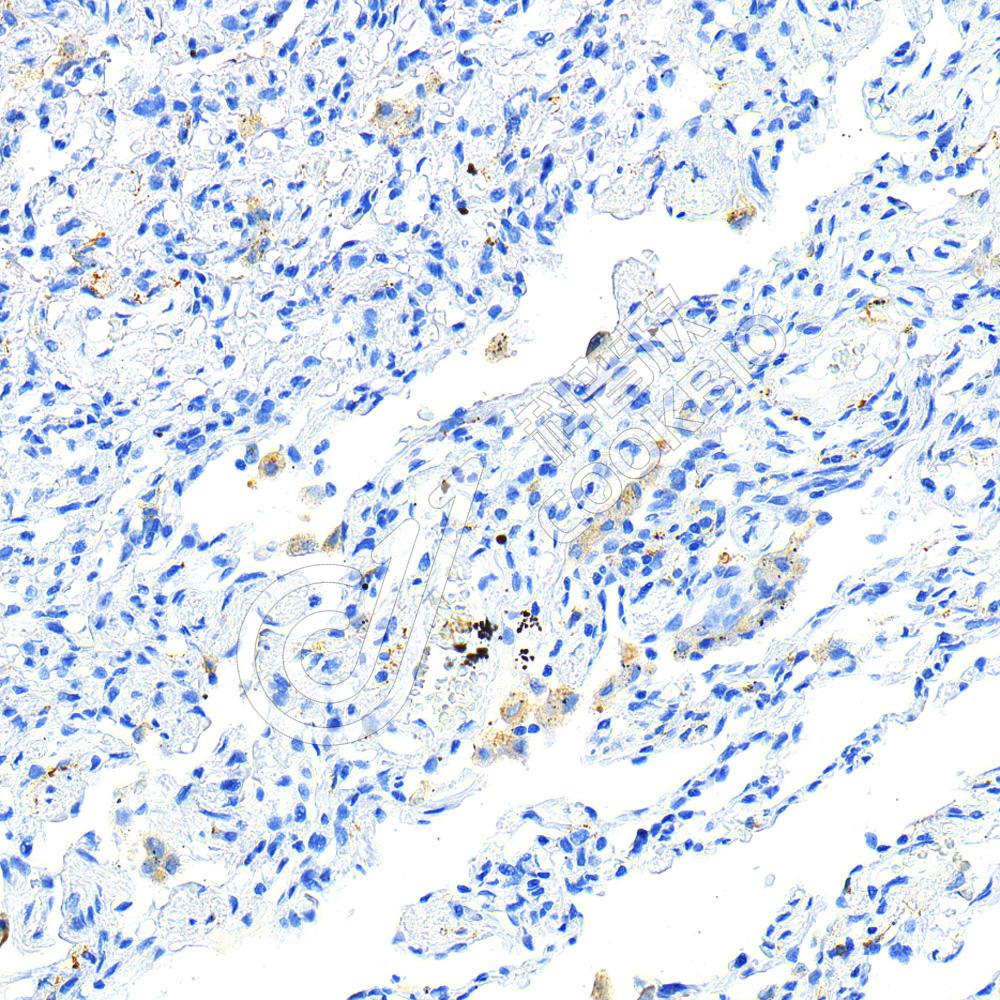

IHC检测Mannose Receptor/CD206蛋白(货号 K2370491).

样品: 人肺, 4%多聚甲醛 (货号KSG1101) 固定12-24小时.

抗原修复: 柠檬酸抗原修复液(干粉, pH 6.0) (KSG1201), 高压锅均匀喷气计时2分钟.

—抗: 1: 1000稀释, 4℃ 孵育过夜.

二抗: HRP标记山羊抗大鼠IgG (H+L) (货号KB69906), 1: 5000稀释, 室温孵育1小时.